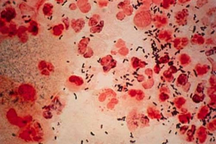

Đánh giá đây là trường hợp cực kỳ hiếm gặp, ekip điều trị đã hội chẩn đa chuyên khoa và quyết định phẫu thuật cắt bướu tinh hoàn bên trái cho bệnh nhân. Quá trình phẫu thuật, ekip phát hiện bệnh nhân còn có buồng trứng bên phải và không có tử cung. Kết quả giải phẫu bệnh là bướu ác tinh hoàn (seminoma - một dạng ung thư tế bào mầm ở tinh hoàn, thường gặp ở nam giới trẻ tuổi).